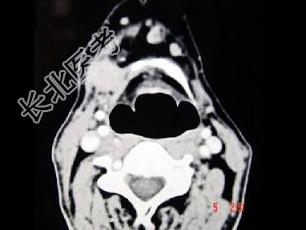

- 单项选择题男,45岁, 右侧颌下扪及一包块约4个月,无痛, PE:包块质硬, 表面欠光整,移动度较差, CT如图所示,最可能的诊断是 ( )